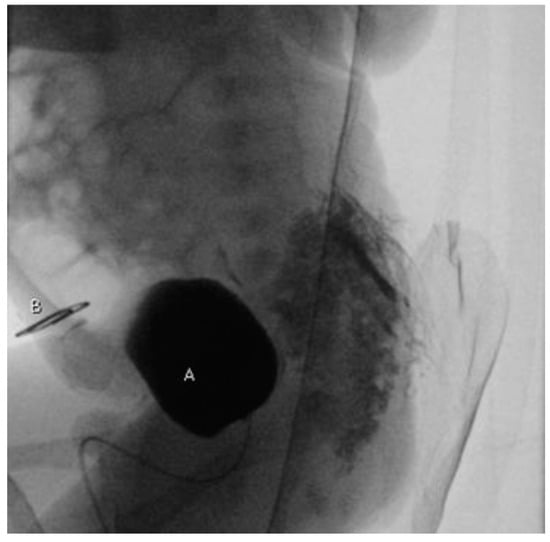

2. Case Report